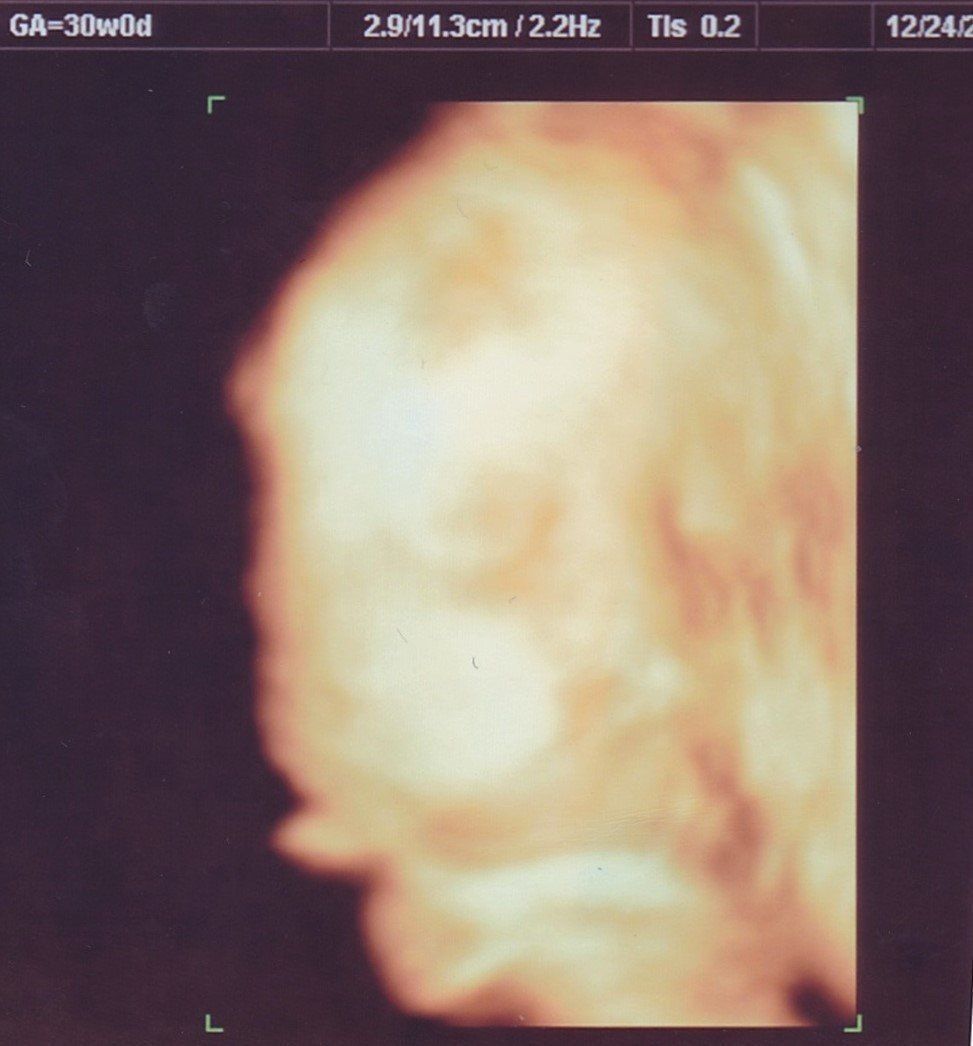

妊娠30週目のエコー写真

赤ちゃんの大きさは標準の真ん中あたり。胎盤の位置や羊水の量も正常、母子ともに問題はありませんでした。

ムチムチの赤ちゃんの顔がアップになった4D写真。出産まで3カ月をきり、改めて「出産準備をしなければ」と、焦り始めました。